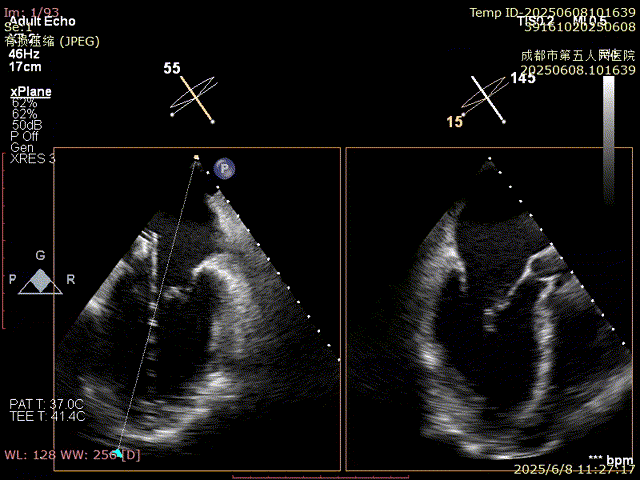

使用二尖瓣夾進行瓣葉捕獲,并進行夾合

確認夾合位置及效果